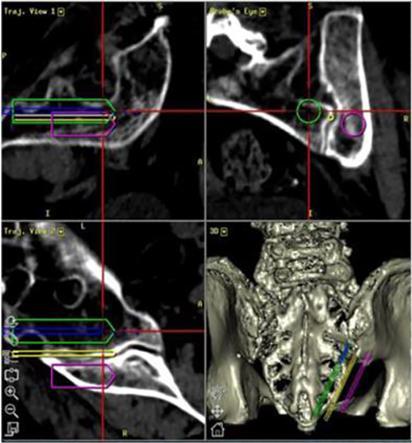

Tenon also has developed a proprietary 2D placement protocol as well as a protocol for 3D navigation utilizing the latest techniques in spine surgery. These Tenon advancements are intended to further enhance the safety of the procedure and encourage more physicians to adopt the procedure.